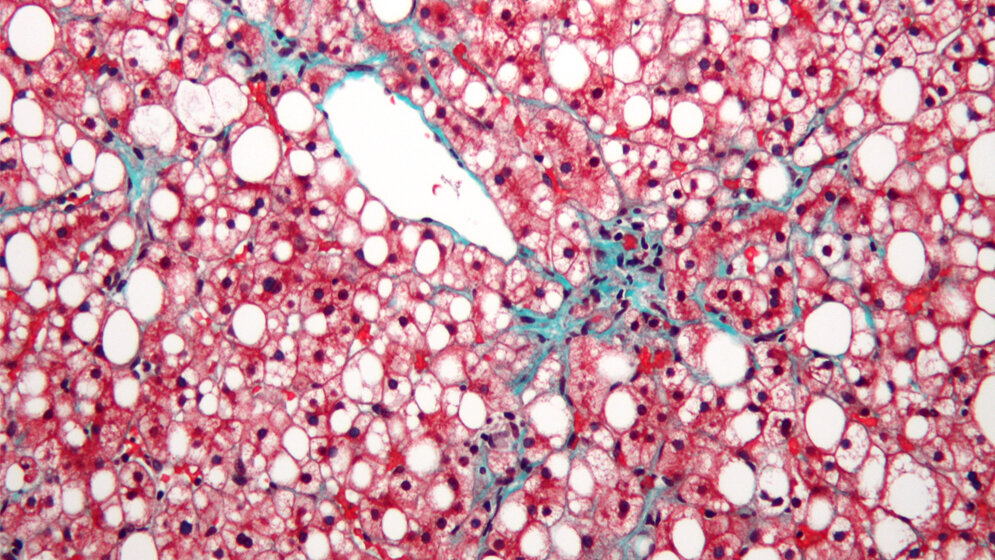

Die nicht-alkoholische Fettleber (NAFLD), auch Steatosis genannt, ist eine unterschätzte Lebererkrankung, die jedoch weltweit auf dem Vormarsch ist. Sie wird häufig mit Übergewicht und Typ-2 Diabetes assoziiert. In westlichen Ländern ist ca. ein Drittel der Bevölkerung von der Krankheit betroffen – oft ohne es zu bemerken. Als Folge von einer kalorienreichen Ernährung bei gleichzeitigem Bewegungsmangel beginnt die Leber Fetttröpfchen einzulagern. Dies ist zunächst harmlos, kann sich aber über die Zeit zu entzündlichen Lebererkrankungen weiterentwickeln. Hieraus können Fibrose, Leberzirrhose und sogar Leberkrebs entstehen.

Mit ihrem Modellsystem konnten die Forscher wichtige Schritte der Erkrankung nachvollziehen: Zum Beispiel die Hochregulation von PLIN2 – einem Protein, das Fetttröpfchen umschließt. Mäuse, die kein PLIN2 besitzen, werden nicht dick – auch nicht, wenn sie große Mengen fettreicher Nahrung fressen. „Wir können mit unserem System sehr effizient die Fetteinlagerung in hepatozytenähnlichen Zellen induzieren und beteiligte Proteine oder microRNAs durch Zugabe verschiedener Faktoren manipulieren. Dadurch ist dieses in vitro Modell hervorragend geeignet zur Erforschung von Medikamenten, die die Einlagerung von Fett in der Leber hemmen“, erklärt Dr. Graffmann.